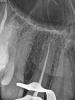

Мартовский Опубликовано 12 октября, 2012 Автор Поделиться Опубликовано 12 октября, 2012 http://s006.radikal.ru/i215/1011/be/08b0eae29281.jpg http://s52.radikal.ru/i136/1011/dc/09f9d15e705f.jpg http://i061.radikal.ru/1210/12/bdb376ccc280.jpg 2 Ссылка на комментарий

Каплан Опубликовано 12 октября, 2012 Поделиться Опубликовано 12 октября, 2012 почти 2 года. как думаете еще уменьшится? Ссылка на комментарий

Мартовский Опубликовано 12 октября, 2012 Автор Поделиться Опубликовано 12 октября, 2012 Я не предсказатель, не знаю. Но динамика то положительная. Ссылка на комментарий

Каплан Опубликовано 12 октября, 2012 Поделиться Опубликовано 12 октября, 2012 Я не предсказатель, не знаю. Но динамика то положительная.я бы сказал суперположительная ттт Ссылка на комментарий

Снежана Опубликовано 15 октября, 2012 Поделиться Опубликовано 15 октября, 2012 Здорово, что вы показали отсроченный результат, спасибо.безусловно положительная динамика есть, очаг стал намного меньше. но если честно, то за 2 года могло бы и совсем восстановиться. мне кажется что вышедший за апекс фрагмент играет свою роль. хотя теперь уже сложно и на апикальную хирургию решиться. может и восстановится до конца. Ссылка на комментарий

Мартовский Опубликовано 15 октября, 2012 Автор Поделиться Опубликовано 15 октября, 2012 Здорово, что вы показали отсроченный результат, спасибо.безусловно положительная динамика есть, очаг стал намного меньше. но если честно, то за 2 года могло бы и совсем восстановиться. мне кажется что вышедший за апекс фрагмент играет свою роль. хотя теперь уже сложно и на апикальную хирургию решиться. может и восстановится до конца.Да, безусловно за два года такие очаги полностью закрываются. Но это обычно, а здесь случай не совсем обычный, да и отношение, как я раньше говорил, у пациентки так себе... Ссылка на комментарий

Kivilgar Опубликовано 15 октября, 2012 Поделиться Опубликовано 15 октября, 2012 Да, безусловно за два года такие очаги полностью закрываются. Но это обычно, а здесь случай не совсем обычный, да и отношение, как я раньше говорил, у пациентки так себе...Если не ошибаюсь критическим сроком для восстановления считается 4 года. Ссылка на комментарий